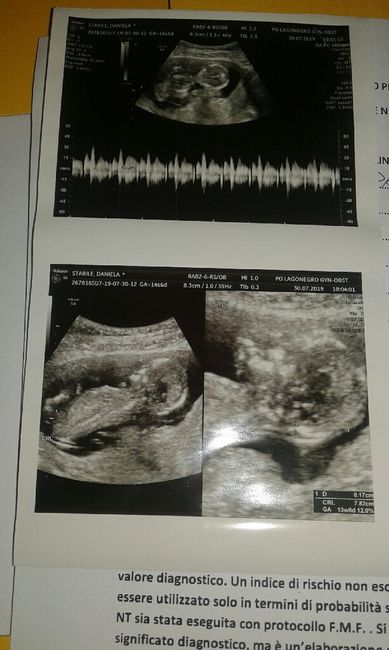

Secondo questa teoria cosa potrebbe essere? Boy or Girl? 💙🎀 Giochiamo un po' 🙂...